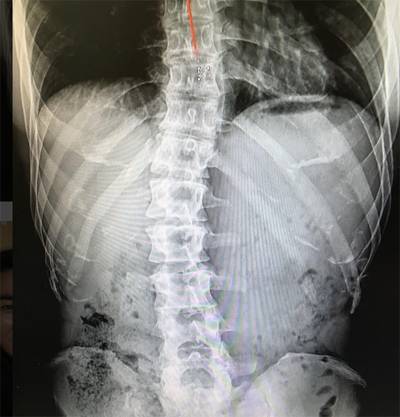

군대와 관련된 악성 댓글에 10년 동안 대응하지 않던 김종국은 4일 자신의 인스타그램에 척추 X-레이 사진을 공개했다.

사진 속 척추뼈는 C자 형태로 심각하게 휘어 있다.

그는 “고등학교 때 처음 허리통증으로 쓰러졌을 때부터 쭉 가지고 있던 척추측만증”이라면서 “이 휘어진 척추를 뭔가로는 잡아줘야 하기 때문에 몸을 만들었다”고 설명했다.